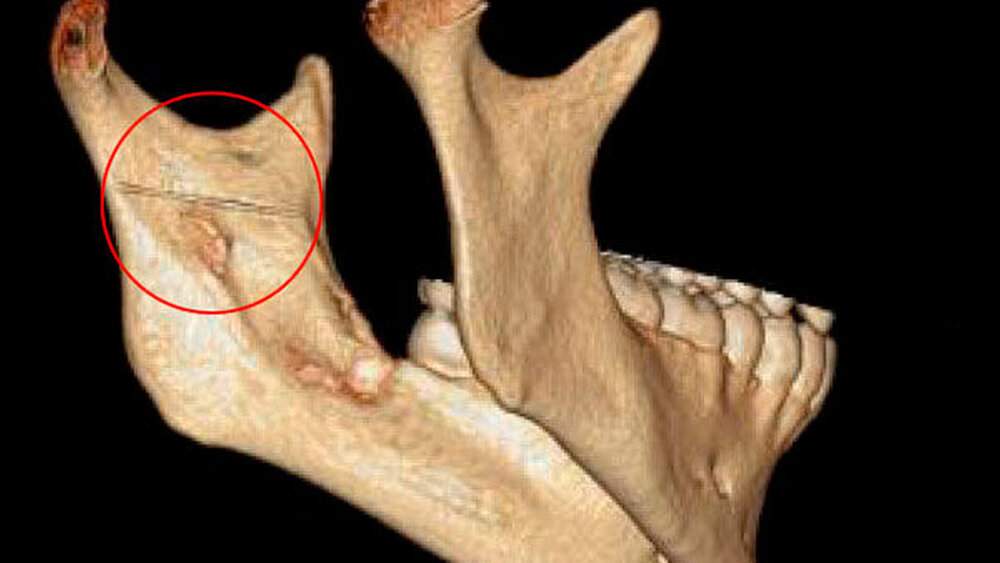

Wir berichten über den Fall eines 29-jährigen Patienten, welcher notfallmäßig vom niedergelassenen MKG-Chirurgen nach einer Weisheitszahn-Osteotomie regio 28 und 38 in unsere Klinik überwiesen wurde. Im Rahmen des ambulanten Eingriffs in lokaler Anästhesie wurde eine Leitungsanästhesie im Bereich des Nervus (N.) alveolaris inferior links vorgenommen. Nach erfolgreicher Osteotomie des linken unteren Weisheitszahns imponierte in der postoperativen Röntgenkontrolle (Orthopantomogramm) ein circa 2,5 cm langer metallischer Fremdkörper im Bereich des aufsteigenden Unterkieferastes links (Abbildung 1).

Hier zeigte sich als Corpus alienum die frakturierte Kanüle in unveränderter Position im Bereich der medialen Seite des aufsteigenden Unterkieferastes auf Höhe des Foramen mandibulae zwischen Unterkieferknochen und Musculus pterygoideus medialis (Abbildungen 2, 3).